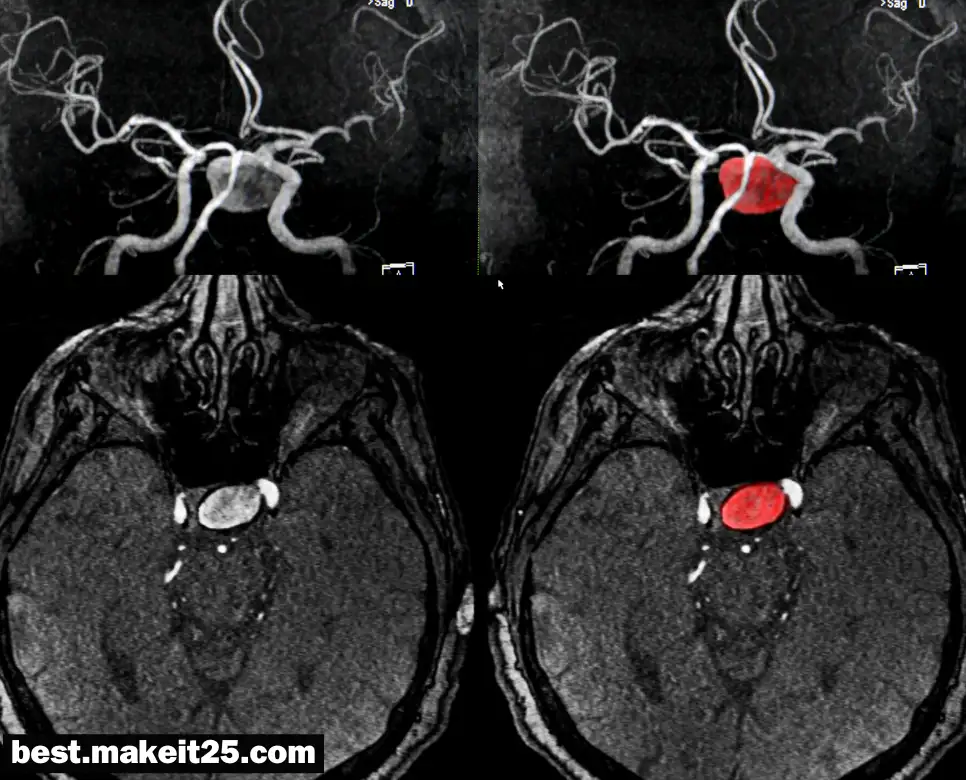

‘MCA’는 Middle Cerebral Artery, 즉 중대뇌동맥을 의미합니다. 중대뇌동맥은 뇌의 주요 혈관 중 하나로, 대뇌 피질의 외측면에 혈액을 공급하는 중요한 역할을 합니다. 이 혈관은 뇌졸중 발생 시 가장 자주 영향을 받는 부위 중 하나로 알려져 있으며, 이로 인한 뇌 손상은 신체의 여러 기능에 영향을 미칠 수 있습니다.

MCA와 관련된 질환으로는 MCA 뇌졸중이 있습니다. 이는 중대뇌동맥이 막히거나 터져서 발생하는 뇌졸중으로, 신체 한쪽의 마비, 언어 장애, 시각 장애 등을 유발할 수 있습니다.

- 진단: MRI, MRA, CTA 등의 영상 진단을 통해 확인할 수 있습니다.

- 치료: 혈전 용해제 투여, 혈전 제거 수술, 재활 치료 등이 있습니다.

MCA는 뇌의 혈액 순환에 있어 중요한 역할을 하며, 관련 질환은 적절한 진단과 치료가 필요한 상태입니다. MCA의 건강은 전반적인 뇌 기능과 밀접한 관련이 있으므로, 이에 대한 이해와 관리가 중요합니다.